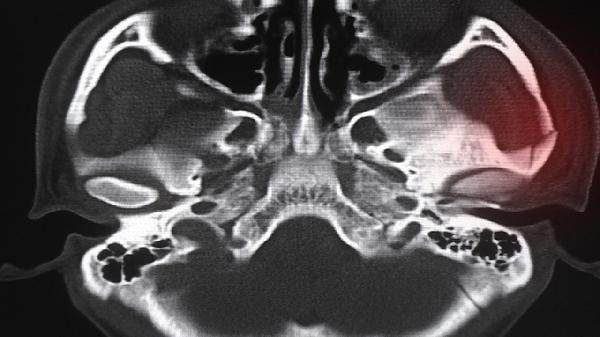

X光检查是判断骨骺线是否闭合的最直接方法。通过拍摄手腕或膝关节的X光片,可以清晰观察到骨骺线的状态。如果骨骺线已经闭合,骨骼的生长空间将消失,身高增长基本停止。建议在专业医生的指导下进行,避免不必要的辐射暴露。